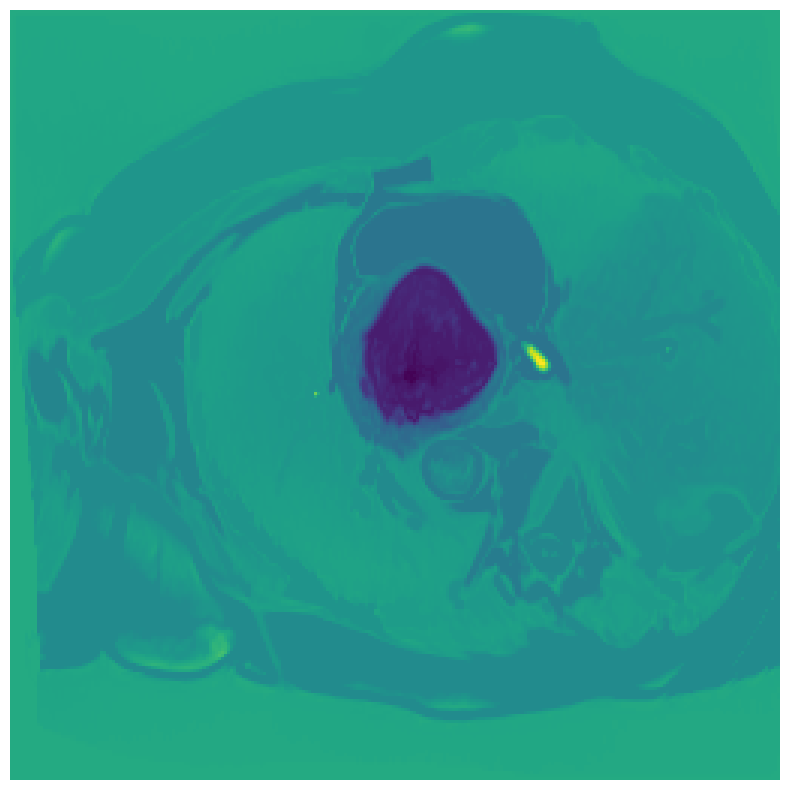

We normalize the volumes and resize the slices to pixels. As the official dataset comes with full annotations, we create a synthetic point ground truth. This is done by first randomly choosing the centers of the point annotations within the class masks, followed by filling an ellipse with axes lengths of and (in pixels) around each center. The intersections of these elliptic discs with the underlying full annotations are then used as our point ground truth. See Figure 2 for an example of the created weak annotation mask. The point annotations are created for every slice, one for each foreground object present in the slice.

5.1 Segmentation of cardiac structures

The average 3D Dice scores and HD95 values on the ACDC test set are given in Table 2, and boxplots in figures 4 and 5 show the distributions. We see that, in terms of DSC, the proposed strategy of using intensity-aware distances withing boundary loss performs better than simply using the Euclidean distance, with the best results achieved by using the strictly intensity based MBD. The HD95 however favors the original version of , which may be do to its smoother predictions and less fragmentation and oversegmentation. The CRF-loss results are significantly worse in both metrics.

In Figure 3 we show the 3D DSC validation curve evolution for a single run. The CRF-loss seems to have converged to a low DSC value, while all settings combining CE and boundary loss reach values close to the full supervision in the beginning of the training and then slowly collapse towards to the point annotations. The MBD version stands out, degrading slower, thus providing a wider range of potentially good models for evaluation.

Qualitative comparison

In Figure 6 we provide qualitative results on a number of randomly chosen test set slices. Upon visual inspection, we can observe that training with the intensity-aware distances (particularly with and ) follows the image gradients better and is better at recovering the underlying shape than the Euclidean version. The CRF-loss seems to recover the shape of the myocardium and left ventricle to some extent, but fails entirely on the right ventricle.